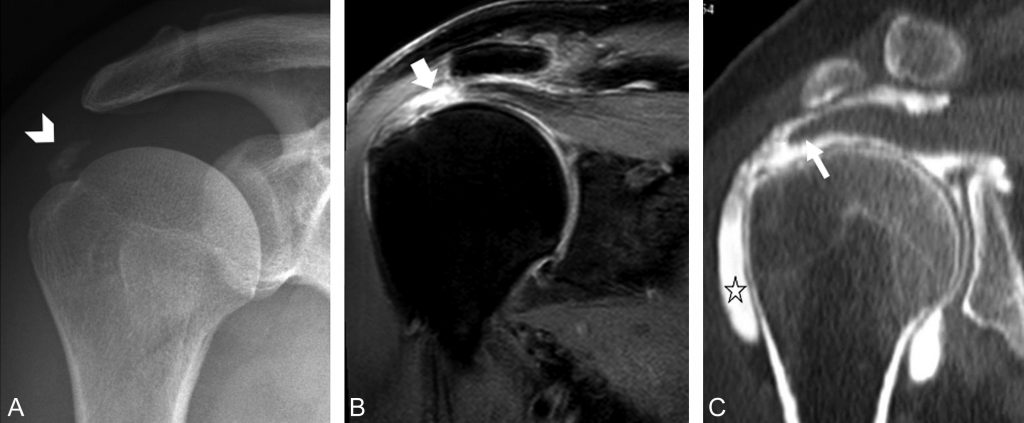

- la tendinopathie est définie par un tendon épaissi en hypersignal T2 non liquidien ;

- la rupture tendineuse est définie par une solution de continuité du tendon. Les fibres tendineuses rompues sont remplacées par un infiltrat liquidien en hypersignal T2 plus intense que dans les tendinopathies (signal équivalent à celui du liquide articulaire) (figure 79.6).

Fig. 79.6 Lésions de la coiffe des rotateurs.

Calcification en projection de l’espace sous-acromial (A), témoin de dépôt de cristaux d’apatite dans le tendon du supra-épineux (tête de flèche). Rupture transfixiante du tendon du muscle supra-épineux (B, C) : IRM (coupe coronale T2 Fat Sat) (B) montrant un hypersignal T2 intense (flèche) représentant l’interruption complète de la partie terminale du tendon du supra-épineux avec passage de liquide articulaire dans la bourse sub-acromio-deltoïdienne ; arthroscanner, reconstruction dans un plan coronal (C), montrant le passage du produit de contraste dans la bourse sub-acromio-deltoïdienne (étoile) témoignant de la rupture complète de la partie terminale du tendon du supra-épineux (flèche).

Source : CERF, CNEBMN, 2022.